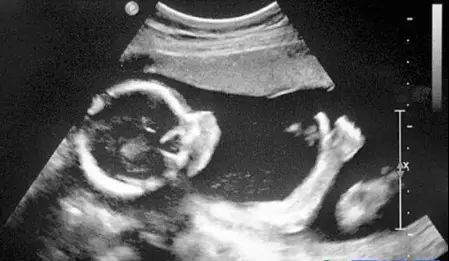

B超针对人体管腔的液体流动和腹腔脏器检查的敏感性较高,我们常常遇到的胆囊结石,肾结石,血管狭窄,心脏功能等等检查,都是B超的用武之地。B超有着独特的优势,便携,可以在床边,甚至在手术中使用。此外,B超市利用超声波成像,也没有所谓的辐射。所以孕妇多采用B超检查。